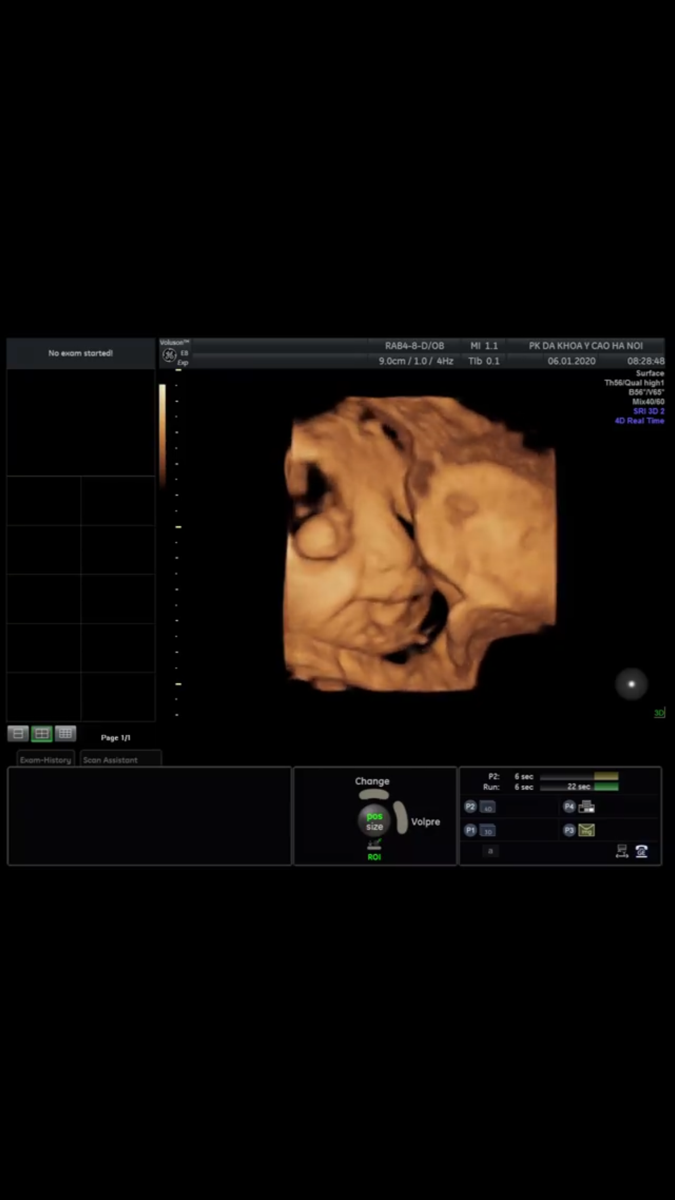

36w4d r, con ngoan . Mong gặp con nhưng con nhớ cũng phải đủ tháng nha. Cả nhà yêu Tít